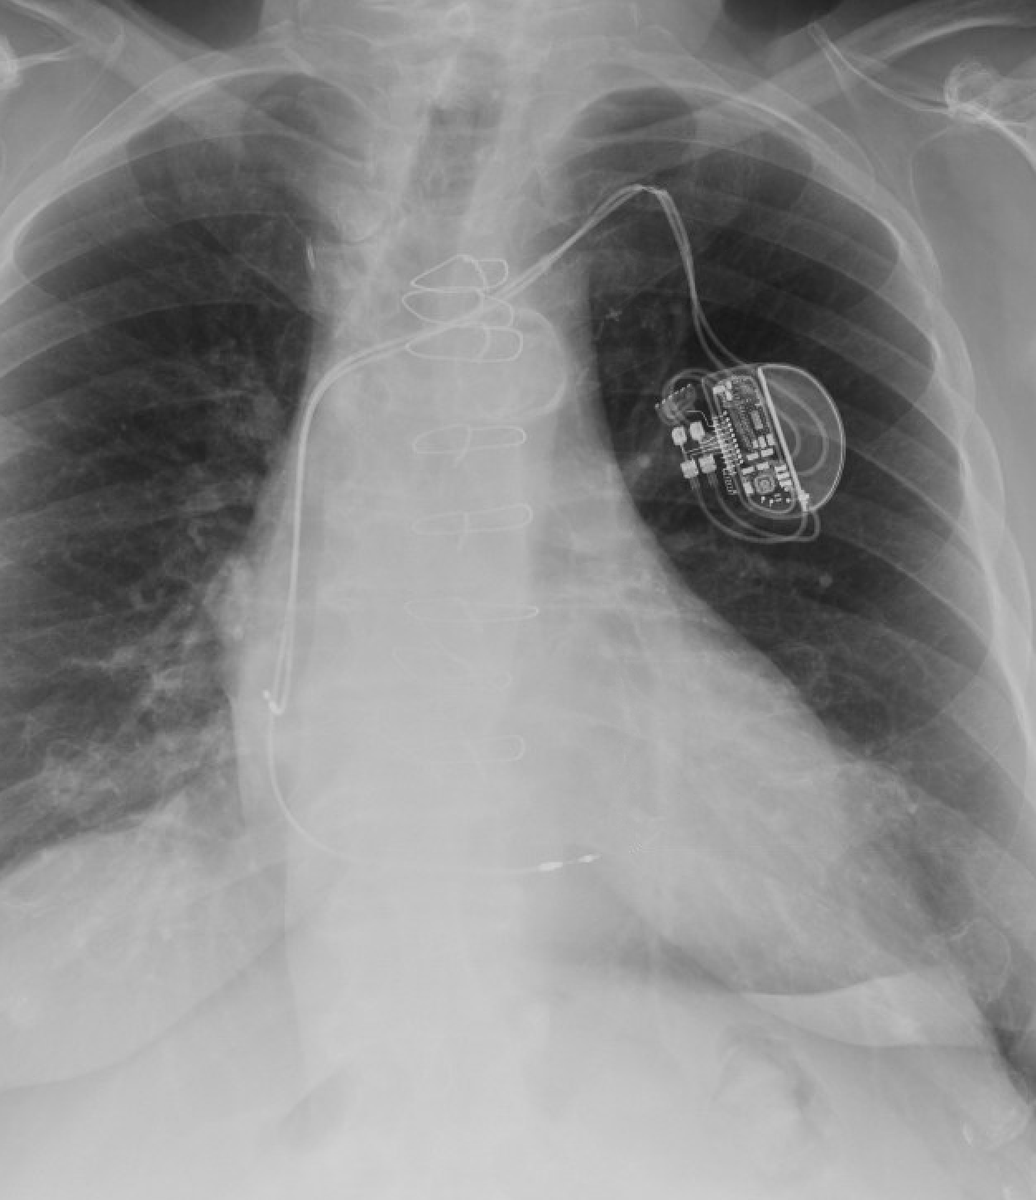

CSP in 2025. Pt with DCM, fibroses, poor EF, VT’s, and 2nd AVB undergoing CRTD with RV shocklead, LBBP and Bachmann bundle pacing.

@JLuermans @lusty63 @Dr_JozaEP @Marek_Jastrz_EP @purerfellner @HaranBurri @Dominik_Linz @MargaridaPujol @DrRoderickTung